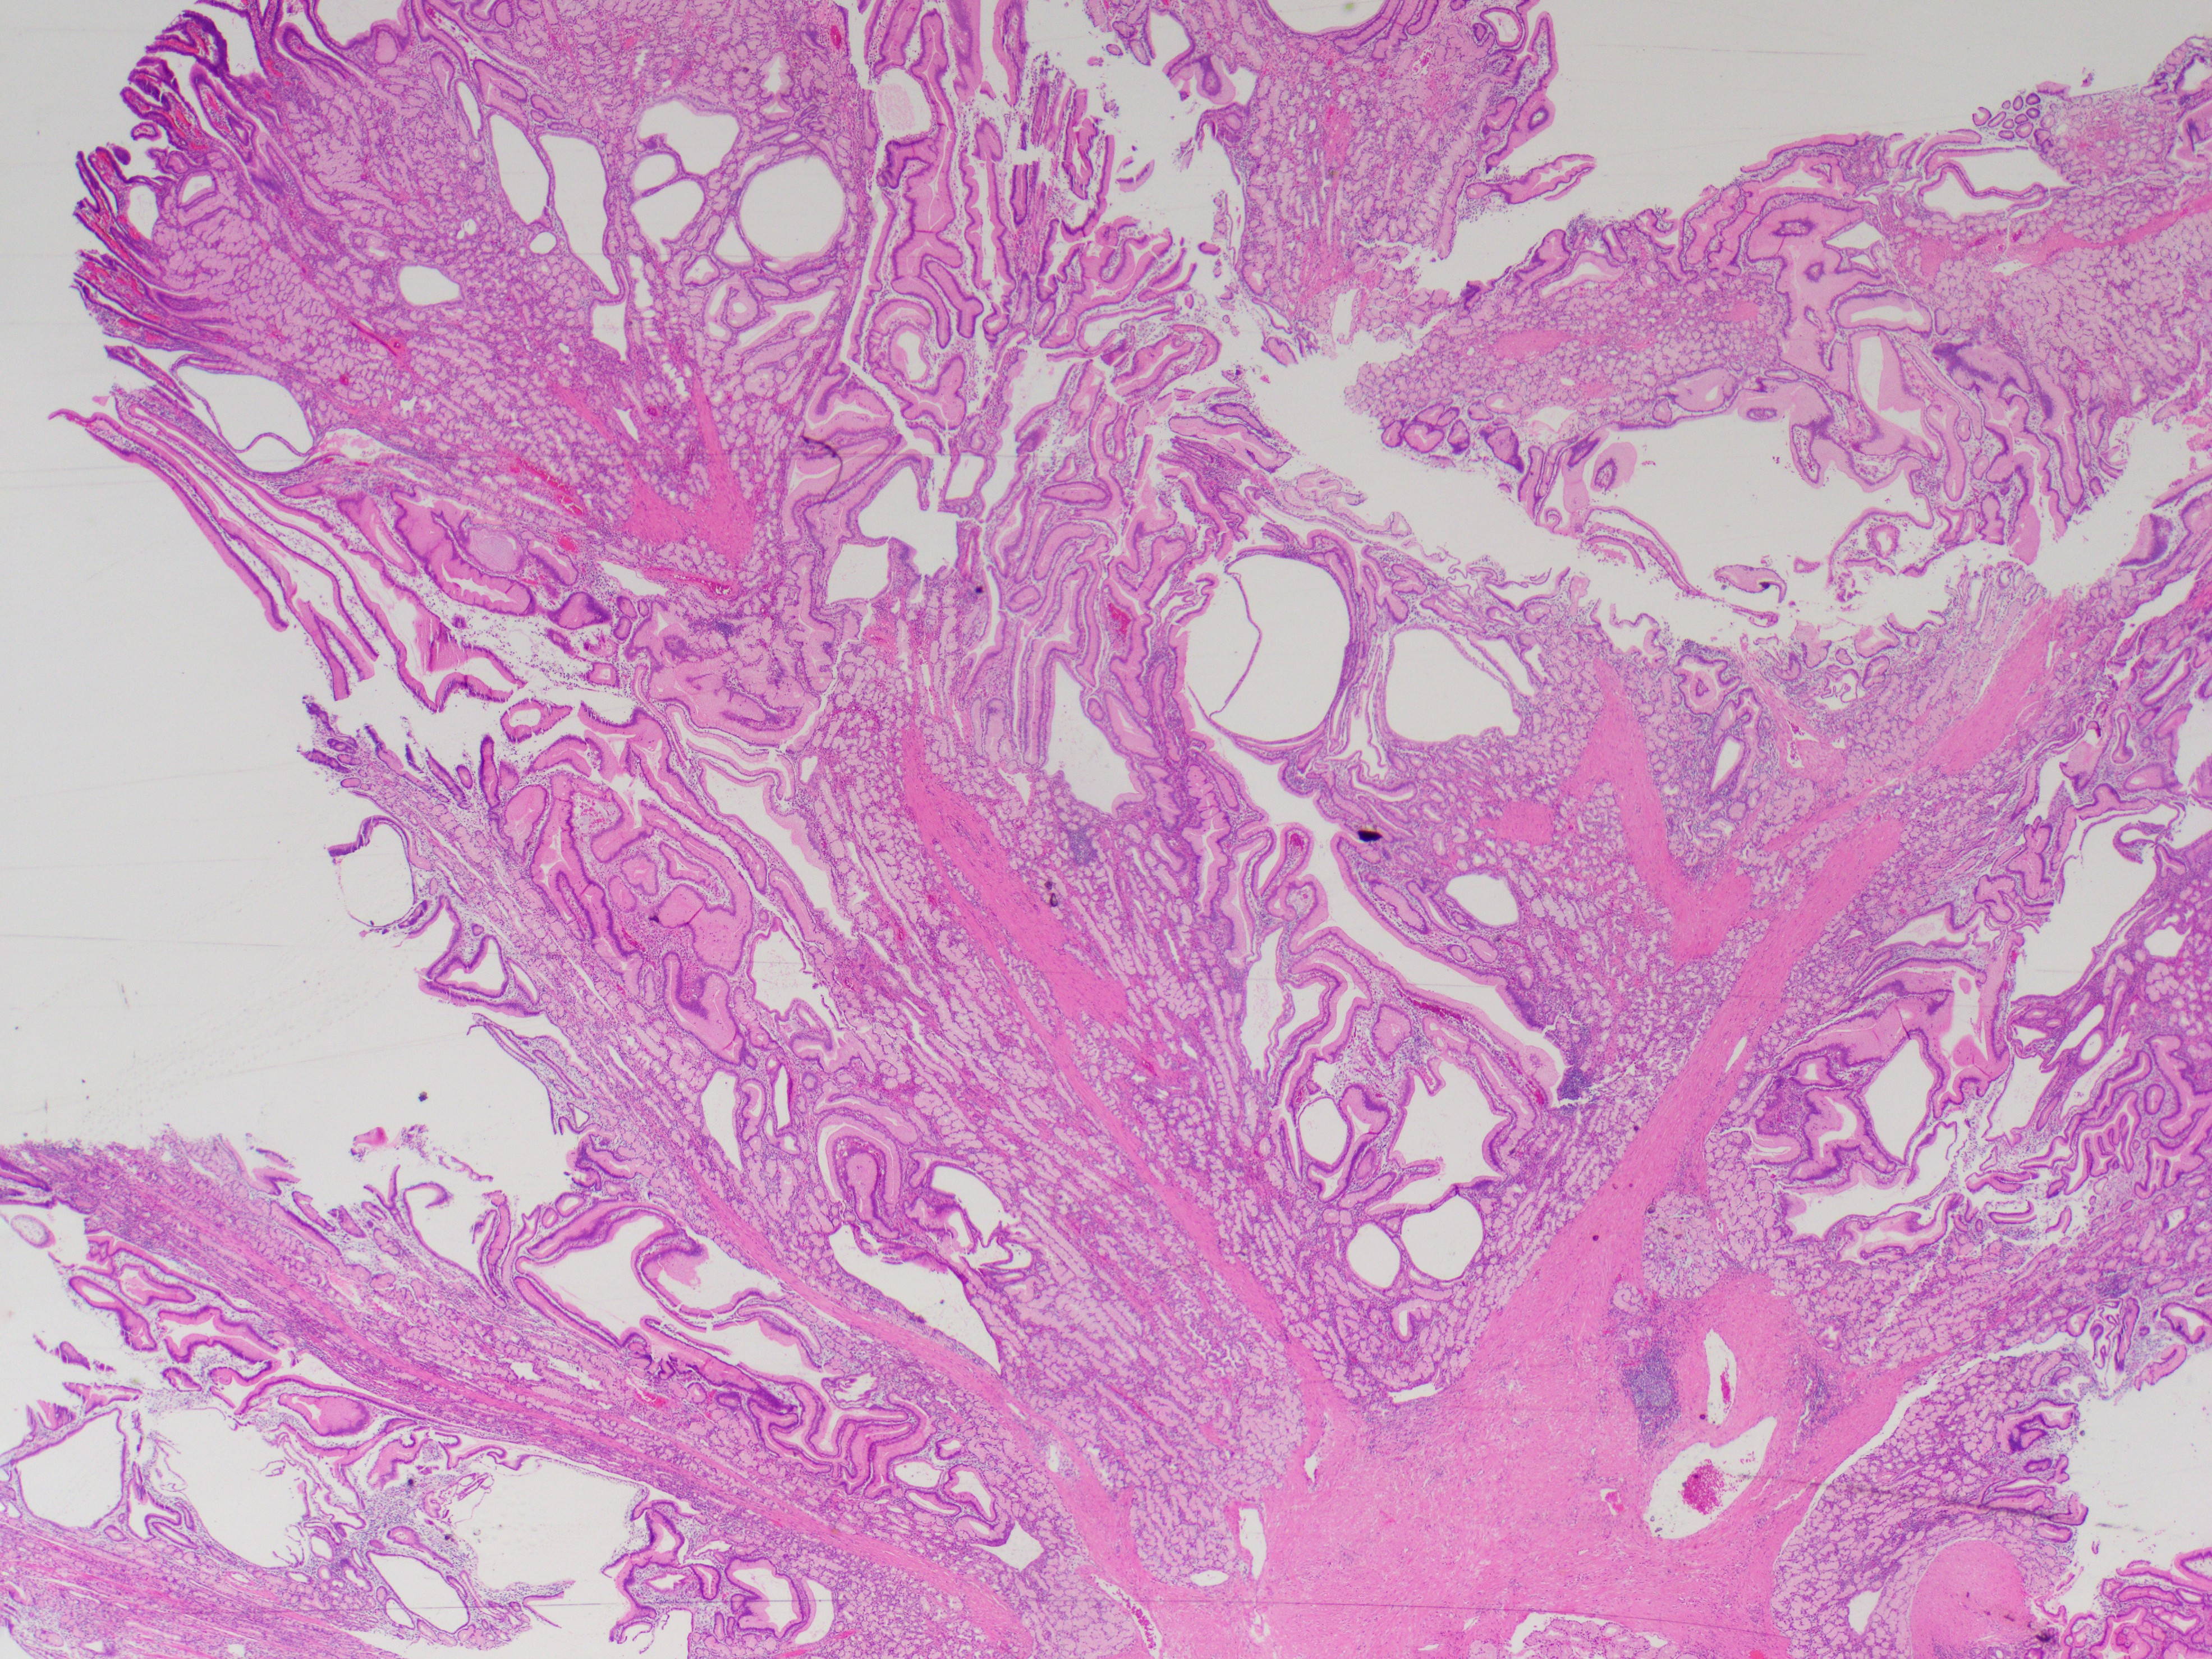

A 40 y/o euthyroid female and a 3 cm left-sided thyroid nodule incidentally found.